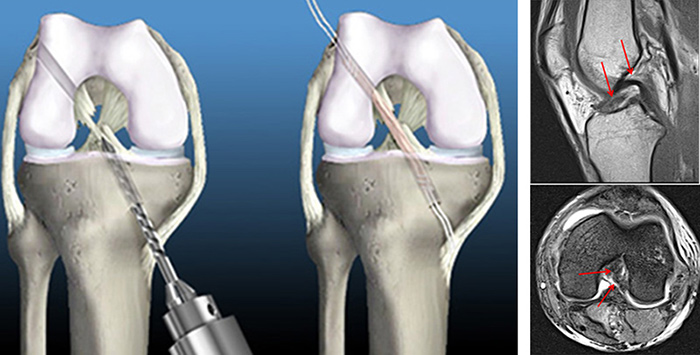

- 전방십자인대 파열의 기전: 체중 부하+비틀림

- 증상: 뚝하는 느낌, 소리, 수상 후 심한 부종, 통증, 혈관절증, 무릎의 불안정한 느낌

- 반드시 인대재건술 필요하며 수술을 하지 않으면 반월상 연골 파열, 관절연골 손상이 유발